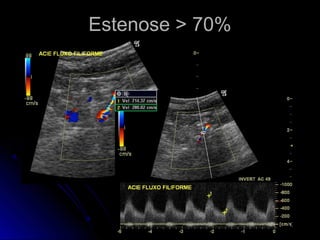

Estenose > 70%Estenose > 70%